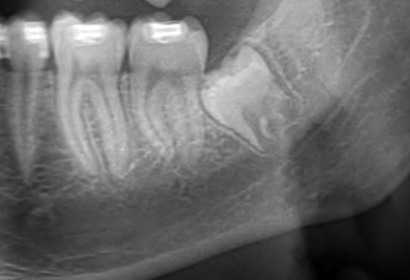

Estrazione Denti Giudizio

I denti del giudizio possono causare dolore e danneggiare i denti vicini: intervenire tempestivamente per proteggere il tuo sorriso.

Offriamo consulenze per valutare la necessità di estrazione dei denti del giudizio.